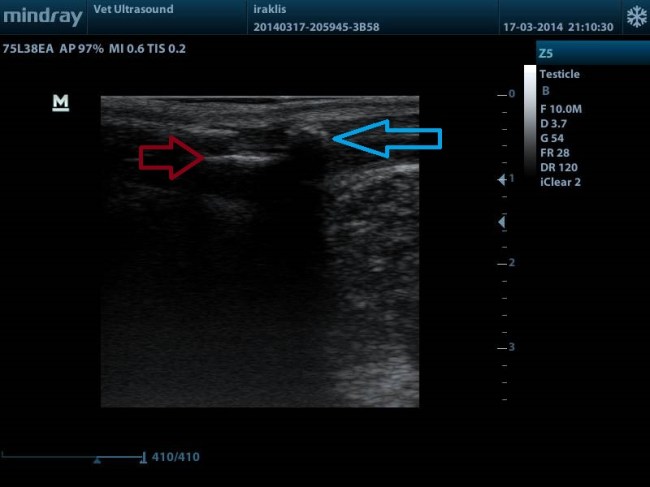

ΤΟ ΚΟΚΚΙΝΟ ΒΕΛΟΣ ΔΕΙΧΝΕΙ ΤΗΝ ΣΚΙΑ ΠΟΥ ΔΗΜΙΟΥΡΓΕΙ ΤΟ ΠΕΪΚΟ ΟΣΤΟ, ΕΝΩ ΤΟ ΜΠΛΕ ΤΟΝ ΛΙΘΟ Ο ΟΠΟΙΟΣ ΕΧΕΙ ΕΝΣΦΗΝΩΘΕΙ ΣΤΗΝ ΟΥΡΗΘΡΑ ΑΚΡΙΒΩΣ ΠΙΣΩ ΑΠΟ ΤΟ ΠΕΪΚΟ ΟΣΤΟ.